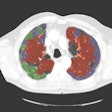

Texture classification eases lung CT analysis

Imaging biomarkers have central role in precision medicine